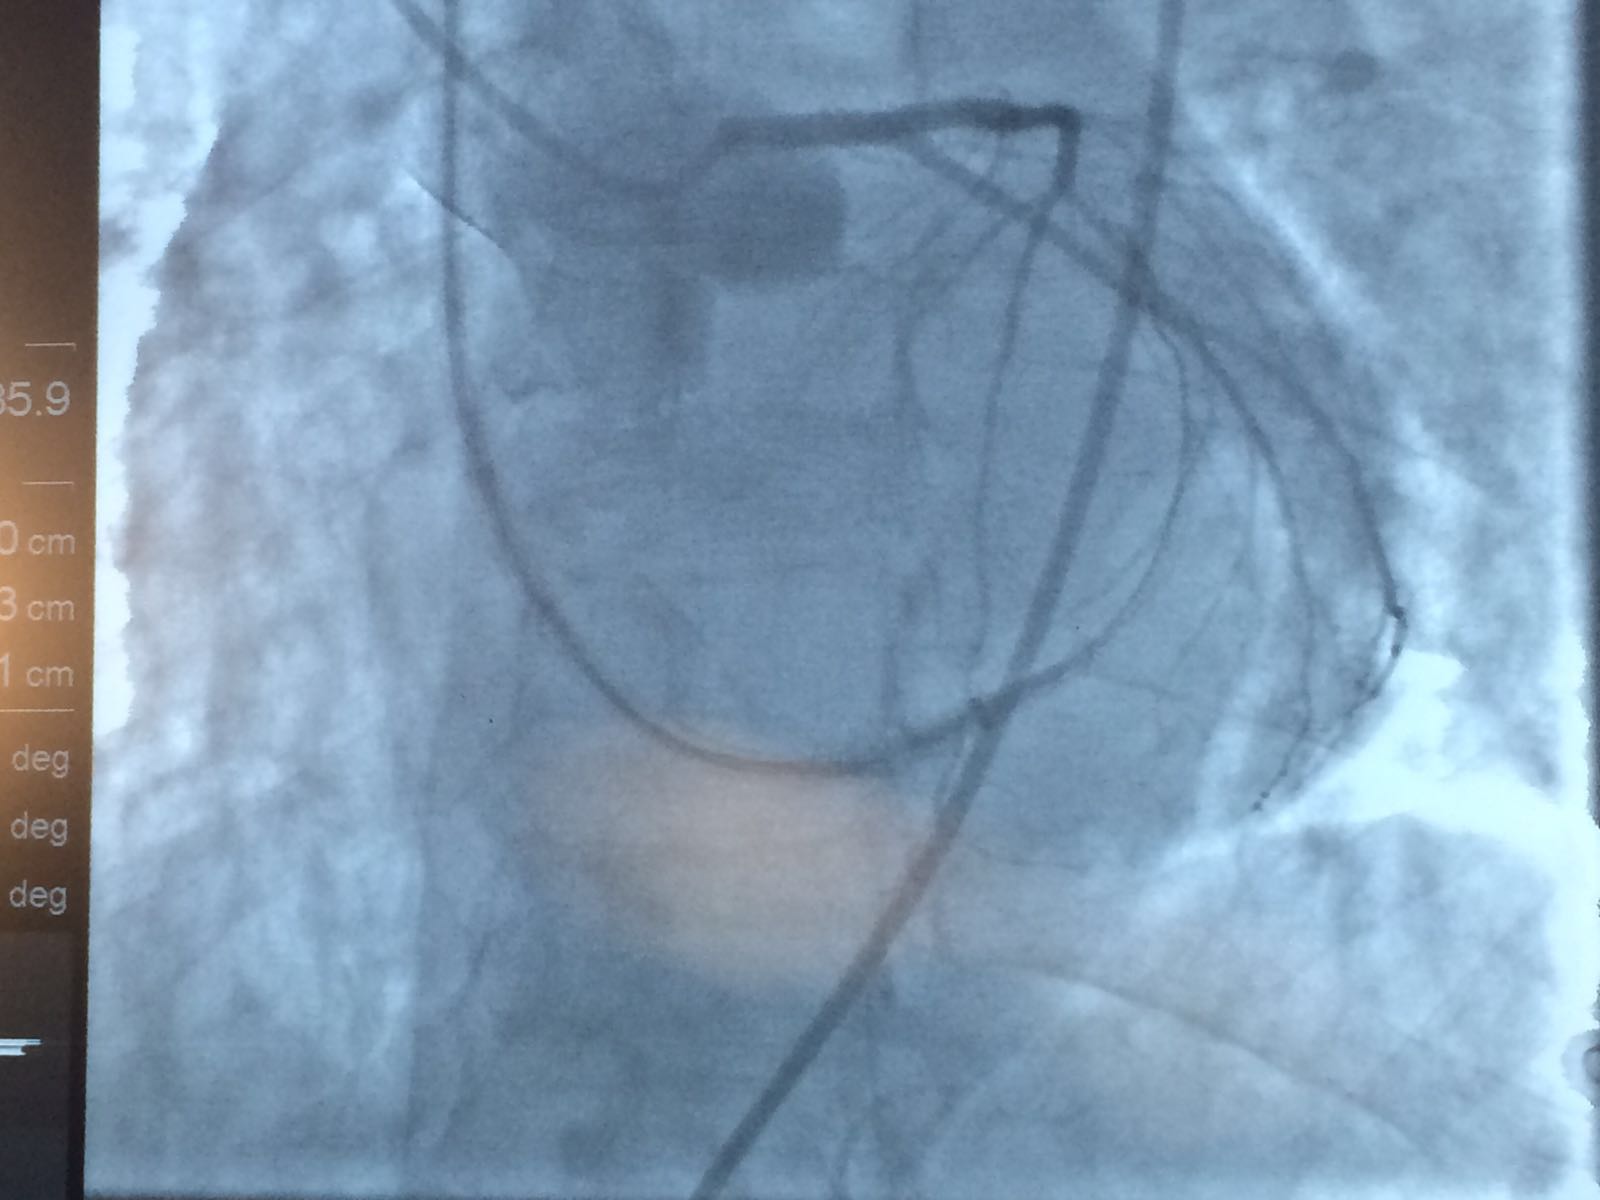

Foto e Video